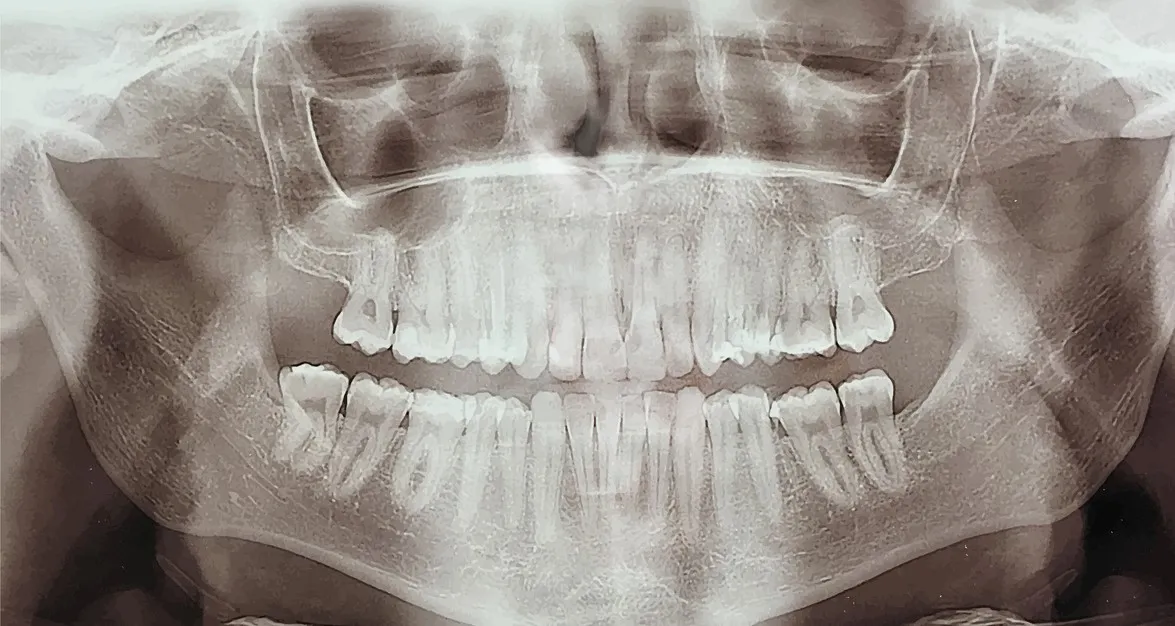

Ortopantomografia e TAC Dentalscan per una indagine dentale completa

Il Poliambulatorio Dalla Rosa Prati è dotato dei più moderni macchinari di diagnostica per le immagini e non fa eccezione per quel che concerne la radiologia dentale.